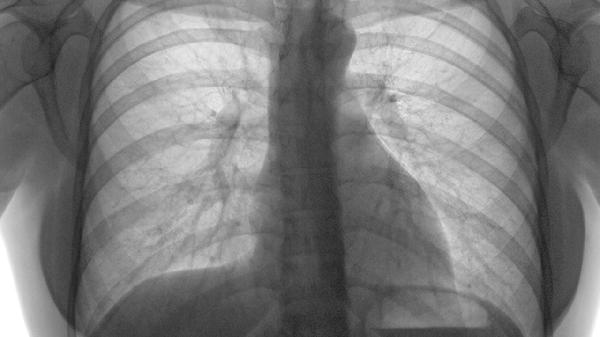

胸肋软骨炎的症状主要有局部疼痛、压痛明显、肿胀隆起。胸肋软骨炎是发生在胸骨与肋骨交界处软骨的炎症反应,多与外伤、慢性劳损或病毒感染有关。